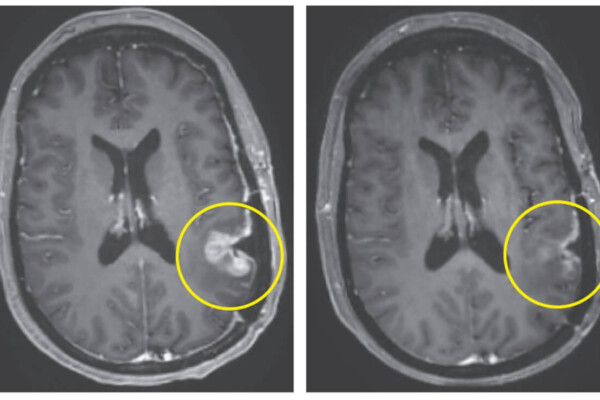

brain cancer tumor scan

Brain Cancer Treatment Almost Completely Eliminates Tumor In Just 5 Days

March 13, 2024